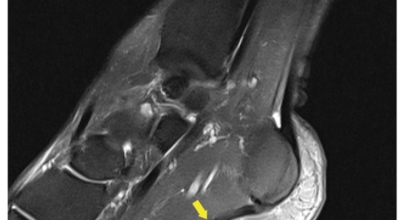

족저 근막이란 발가락 시작지점부터 발뒤꿈치뼈까지 발바닥 전체를 감싸고 있는 두꺼운 막을 말해요. 족저 근막은 발바닥 아치를 지속시켜 발바닥이 지면을 내딛음으로써 나타나는 충격을 흡수하는 중요한 역할을 수행하고 있어요. 이 족저 근막에 일차적으로 서서히 조직 손상이 일어나고 계속적인 활동으로 인해 염증이 커지면서 발 뒤꿈치 부근 통증을 유발하게 되는데 염증은 무리하고 반복적인 동작, 과도한 사용으로 마찰에 의해 발생해요.